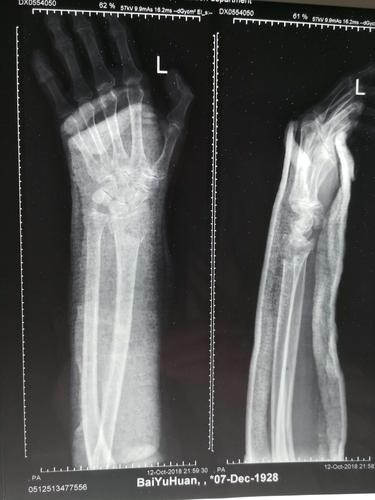

手臂左尺桡骨多段粉碎性骨折